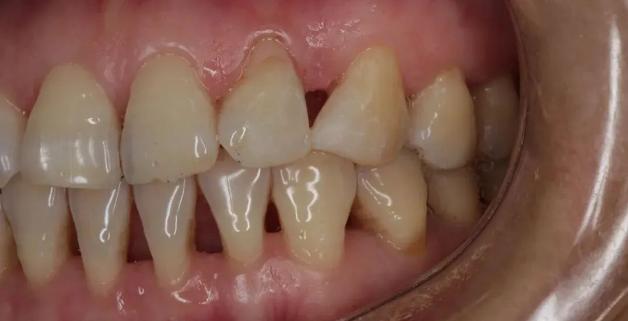

慢慢地,你不在意,牙齦只是有點退縮,然後牙齒縫慢慢顯露出來,露出難看的黑三角。

由於牙齦退縮,牙齒之間形成了黑三角,此時要治療和改善已經非常困難丨作者提供